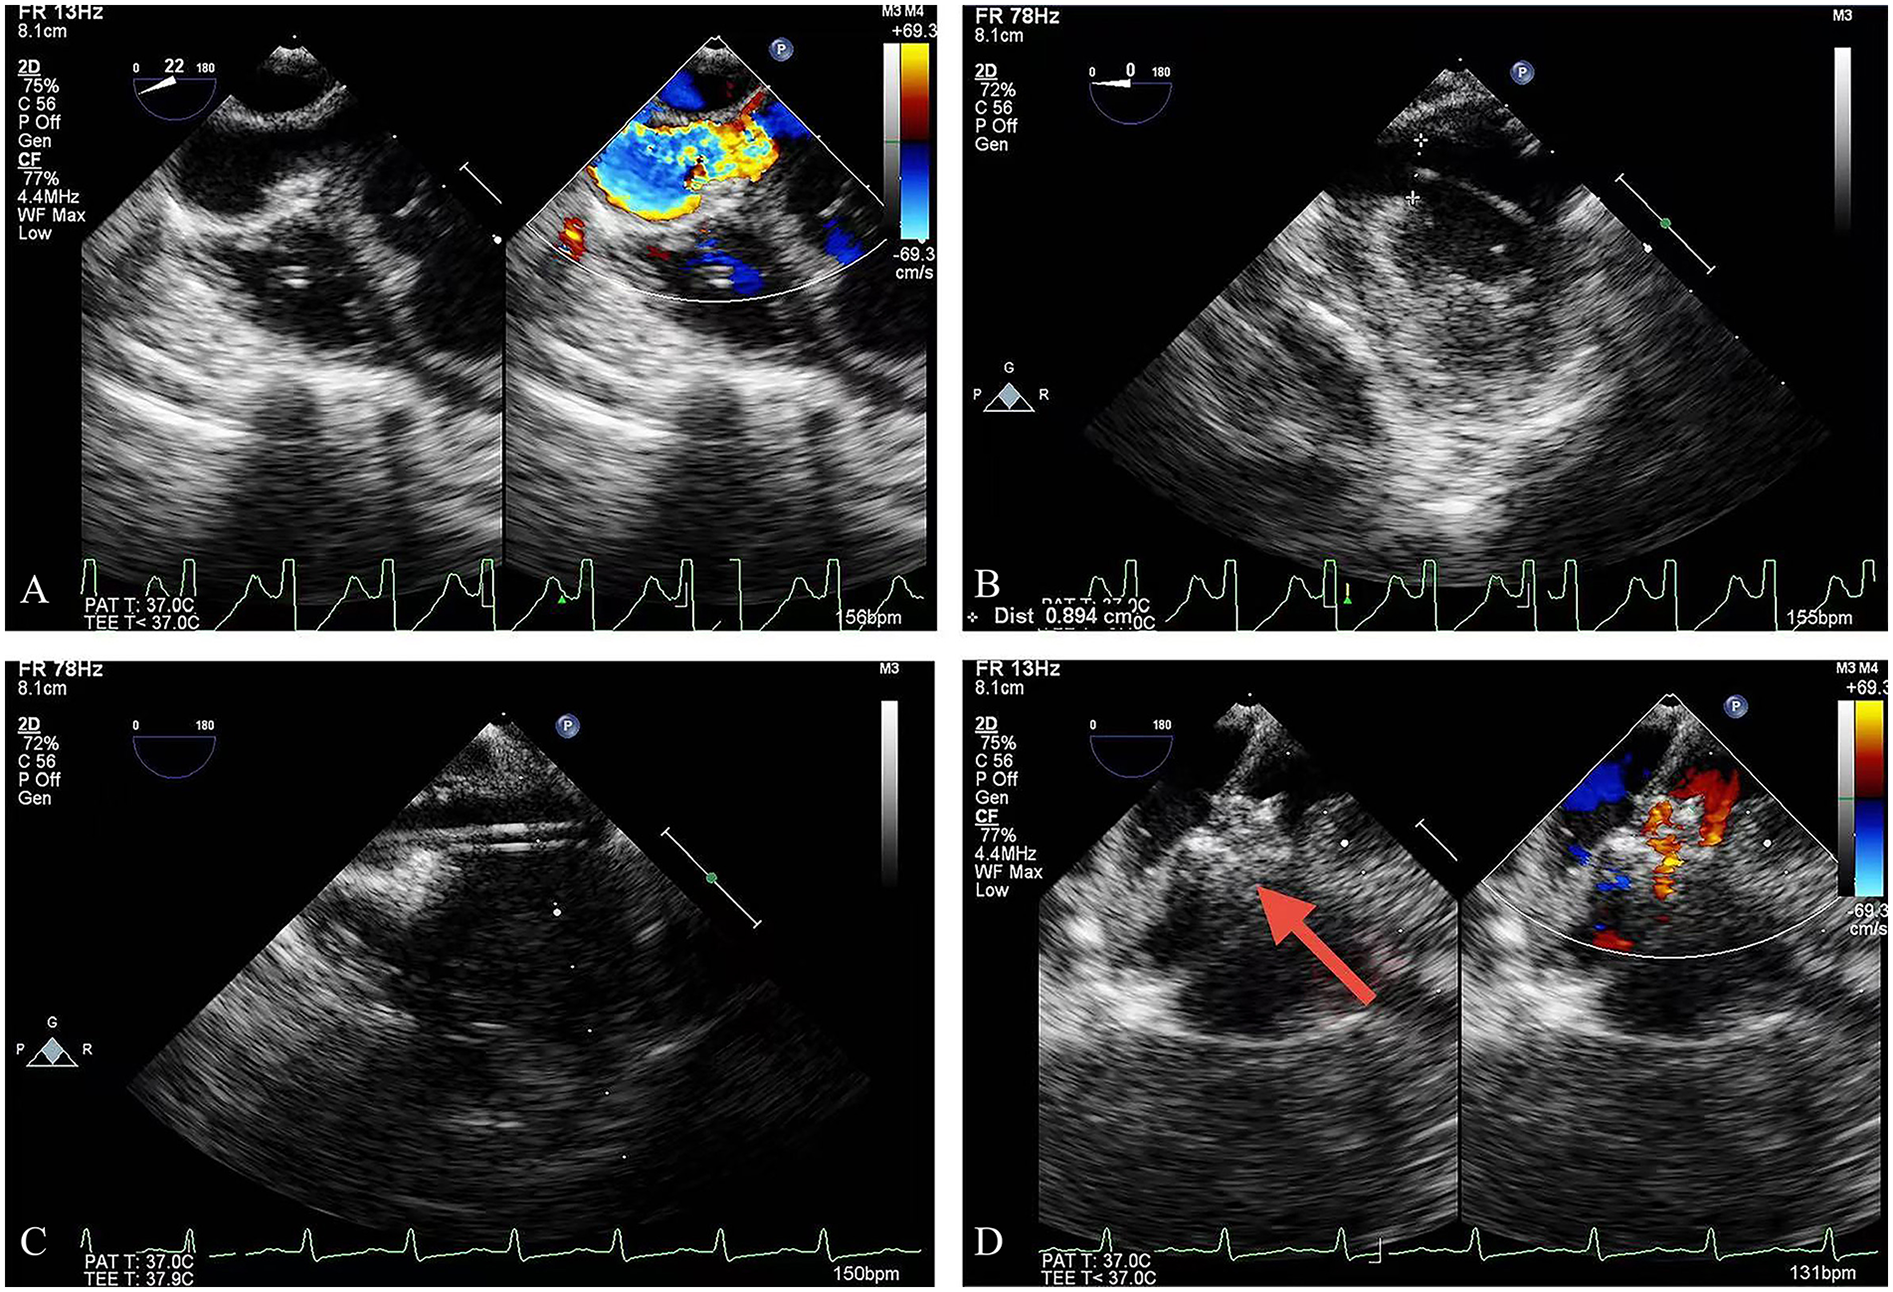

Figure 1

TEE guidance: (A) the outlet of the CAF; (B) the guidewire was advanced into the LV; (C) the delivery sheath was introduced over the guidewire; (D) deployment of the occlusion device (red arrow = device). TEE, transesophageal echocardiography; LV, left ventricle.